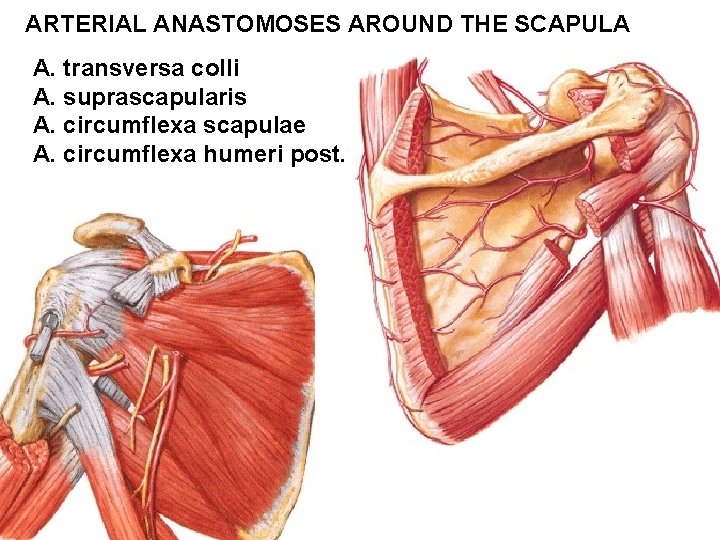

ARTERIAL ANASTOMOSES AROUND THE SCAPULA A. transversa colli A. suprascapularis A. circumflexa scapulae A. circumflexa humeri post.